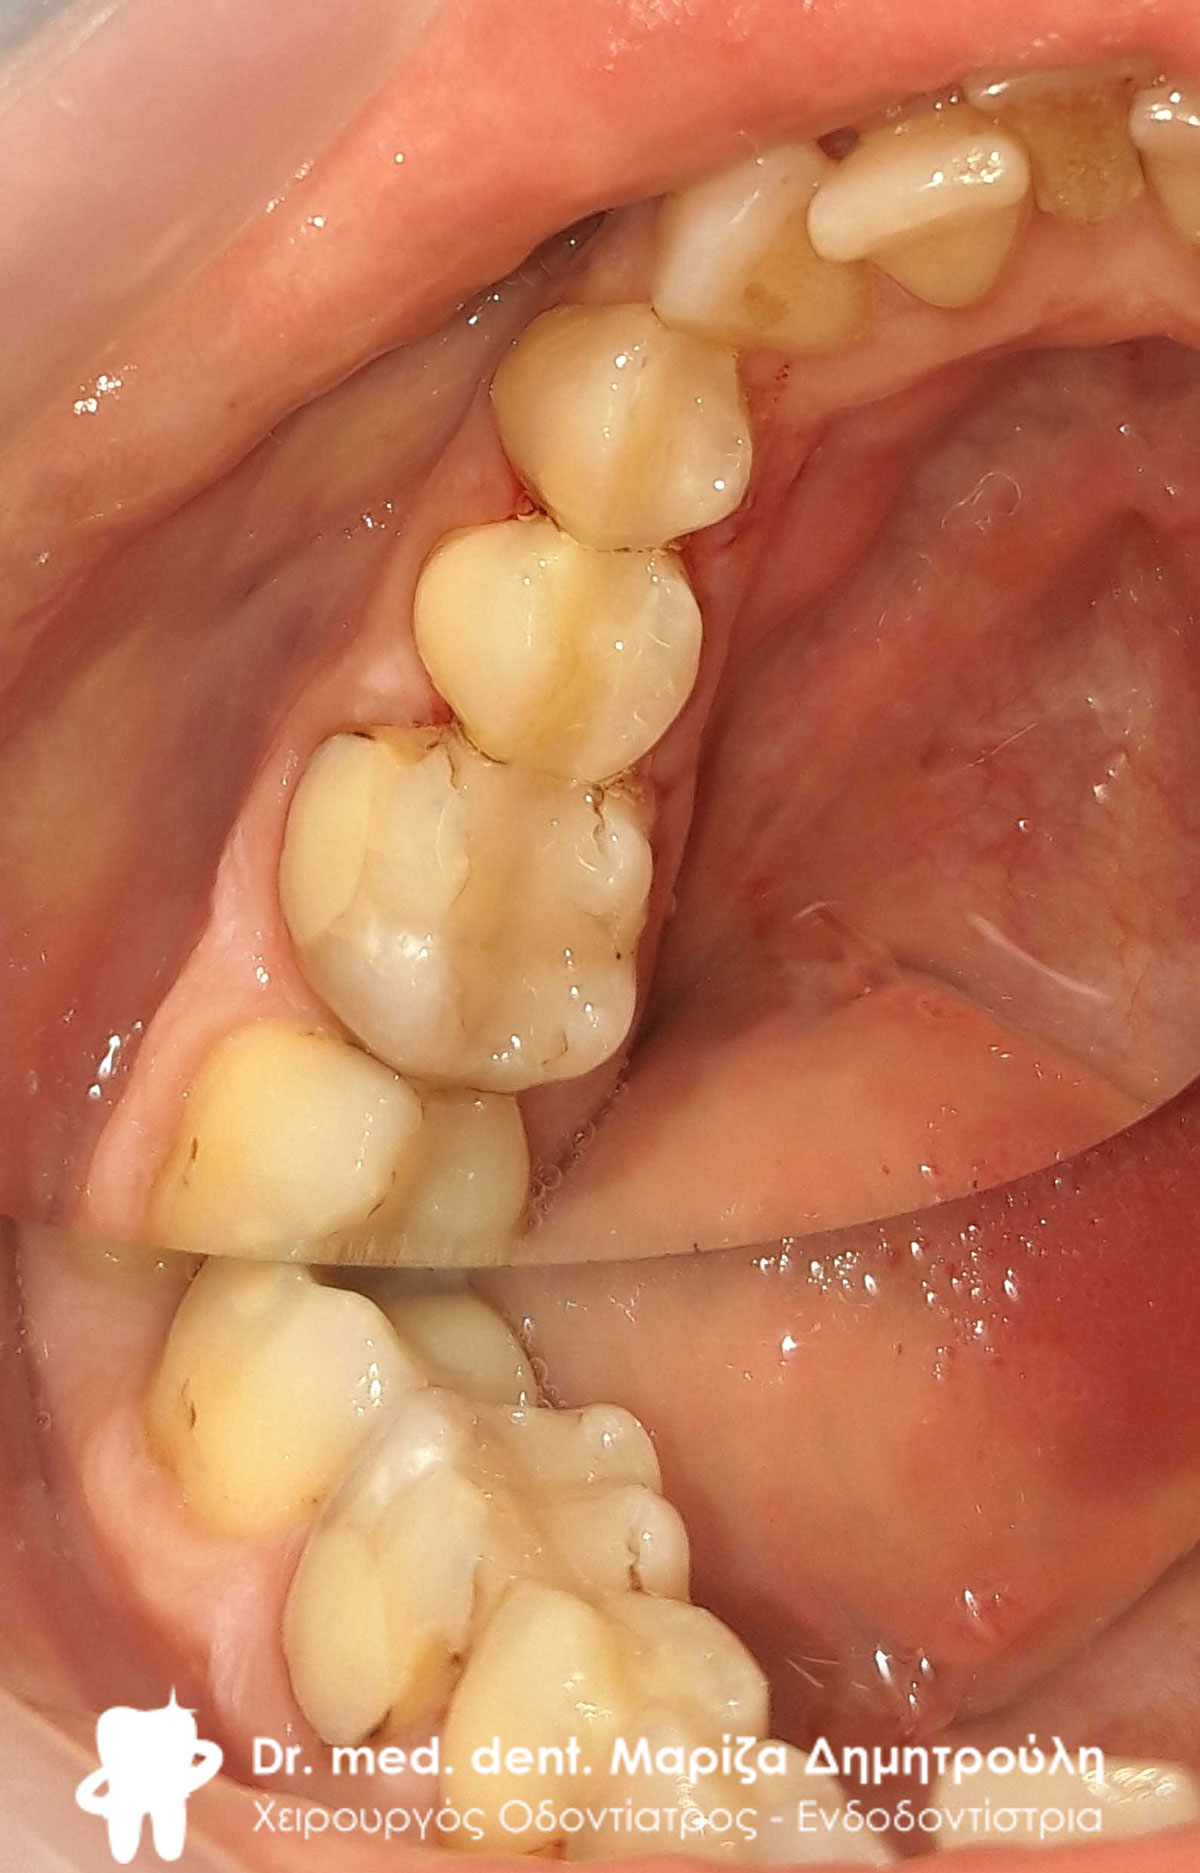

Αρχική κλινική εικόνα της άνω γνάθου

Αρχική κλινική εικόνα της αριστερής πλευράς της άνω γνάθου

Αρχική κλινική εικόνα της δεξιάς πλευράς της άνω γνάθου

Η ασθενής είχε παραμελήσει χρόνια τα δόντια της και πήρε την απόφαση να τα αποκαταστήσει τόσο για αισθητικούς όσο και για λειτουργικούς λόγους.

Περιστατικό – Ολική αποκατάσταση της άνω γνάθου